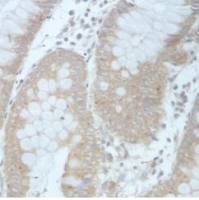

该抗体是针对GHRL的兔多克隆抗体。在免疫组织化学染色和免疫印迹实验中能识别GHRL。

Immunohistochemistry: 5-20µg/mL;1:25-100